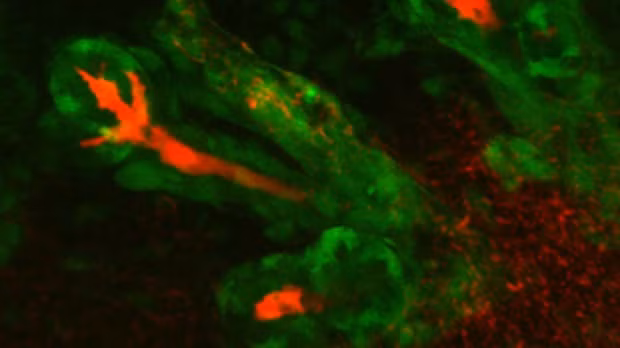

Năm 2013, các nhà khoa học của Viện Công nghệ sinh học phân tử tại Vienna, Áo thông báo họ đã thành công tạo ra một bộ não nhỏ trong phòng thí nghiệm. Bằng cách sử dụng tế bào gốc, họ đã phát triển mô hình một bộ não đang phát triển tương đương kích thước của bộ não của một bào thai lúc chín tuần tuổi.